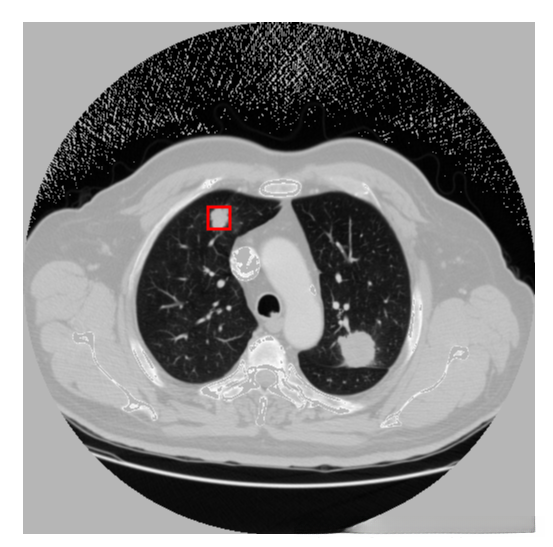

原图:

预测:

标注图(根据标注生成):

在应用yolov3算法进行肺结节检测时,发现其在实际应用中仍存在一定局限性。具体表现为:1)迭代训练不足导致模型尚未达到充分收敛的状态;2)有必要对训练数据集进行聚类分析以优化参数设置,并调整anchor框大小与比例参数设置以进一步提升检测精度。